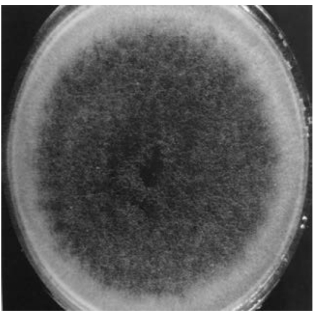

(2)菌落特点:烟曲霉在25℃、37℃甚至45℃培养,均生长良好,发育迅速。菌落呈绒毛状或絮状,开始为白色,经2~3天后转为蓝绿色至烟绿色,成粉末状。烟曲霉菌落形态见图15-11及文后彩图。

图15-11 烟曲霉菌落形态